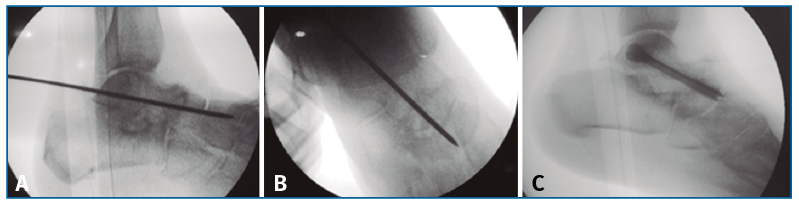

En tercer lugar, una vez realizada la tenotomía de alargamiento del tendón de Aquiles y la liberación y cruentación de las articulaciones TN y ST, se consigue una gran flexibilidad del retropié, previamente rígido, lo que permite realizar la reducción de la deformidad multiplanar, mediante la corrección de la subluxación peritalar propia del estadio III, presionando la cabeza del astrágalo dorsal y lateralmente, al mismo tiempo que el retropié es rotado internamente alrededor del astrágalo y la rotación del antepié corrige la supinación del mismo. La TN es fundamental reducirla perfectamente en posición neutra en ambas proyecciones Rx AP y L.

Finalmente, se realiza la osteosíntesis a compresión con un tornillo (ICOS® 6,5 mm; un caso con tornillo HCS® Synthes 6,5) primero de la TN (Figura 3) y después de la ST (Figura 4)(29)(30).

Figura 3. Reducción y fijación con aguja guía de la articulación astrágalo-escafoidea bajo control fluoroscópico en lateral (A) y anteroposterior (B) y osteosíntesis a compresión con un tornillo (C; ICOS® 6,5 mm).